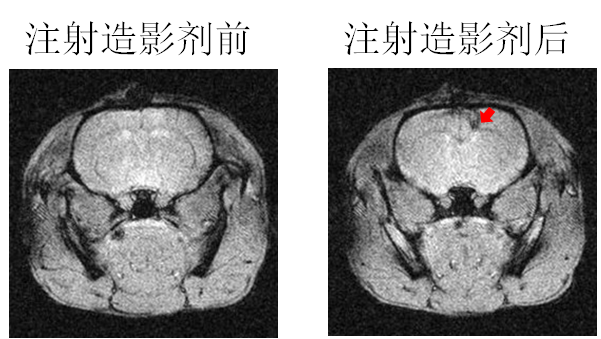

´ÅÐÔÄÉÃ×Á£×ÓÓÃ×÷´Å¹²Õñ³ÉÏñ£¨MRI£©ÔìÓ°¼Á

ÒÔǰֻÊÇÔÚÓ¡ÏóÖУ¬ÎªÁËÕâÊÂÕÒÁËһϣ¬»¹Ã»ÓÐÀ´µÃ¼°ÈÏÕæ¶Á¡£Ï£ÍûÓÐÖú http://www.ema.europa.eu/docs/en ... /01/WC500067464.pdf from wiki: http://en.wikipedia.org/wiki/MRI_contrast_agent Iron oxide: Superparamagnetic[edit] Two types of iron oxide contrast agents exist: superparamagnetic iron oxide (SPIO) and ultrasmall superparamagnetic iron oxide (USPIO). These contrast agents consist of suspended colloids of iron oxide nanoparticles and when injected during imaging reduce the T2 signals of absorbing tissues. SPIO and USPIO contrast agents have been used successfully in some instances for liver tumor enhancement.[17] Although SPIOs and USPIOs have been approved for use in the past, it appears that all of the agents listed below are no longer available with the exception of the oral iron oxide contrast agent, Lumirem/Gastromark. Feridex I.V. (also known as Endorem and ferumoxides). This product was discontinued by AMAG Pharma in November 2008.[18] Resovist (also known as Cliavist). This was approved for the European market in 2001, but production was abandoned in 2009.[19] Sinerem (also known as Combidex). Guerbet withdrew the marketing authorization application for this product in 2007.[20] Lumirem (also known as Gastromark). Gastromark was approved by the FDA in 1996.[21] Clariscan™ (also known as PEG-fero, Feruglose, and NC100150). Development was discontinued due to safety concerns.[22] |